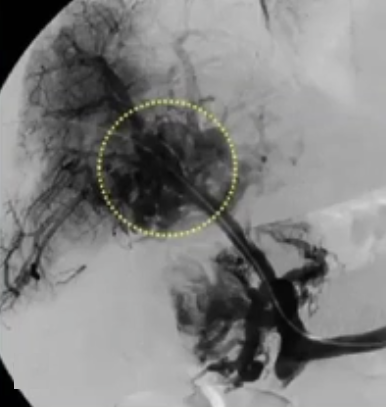

急性病例,已有肠道缺血的迹象,经皮穿刺入路,尿激酶溶栓(t-PA),血流不畅,转为经颈静脉肝内门体分流术(TIPS),抗凝治疗

急性门静脉血栓(续) 对于那些成功实施经颈静脉经肝到达门静脉内急性血栓内,并进行了溶栓和抗凝治疗的患者,是否应该进行经颈静脉肝内门体分流术(TIPS)呢(放支架)? 这一问题存在争议。 。一个过于激进的TIPS手术,导致门静脉分支没有血流,从而发展成肝硬化 妥协的操作是设置一个“小TIPS”,即放置一个直径较细(直径5毫米左右)的TIPS裸支架,溶栓导管经支架通过,进行抗凝和溶栓治疗后,同时保留 TJ 对 SMV/PV 的访问权限,以防再次发生血栓情况。 一例术后急性门静脉血栓病例,最终影像显示门静脉根部血流情况良好,这还不够理想,担心会再次发生血栓,且门静脉压(PSG)超过 12 毫米汞柱,因此增加了经导管动脉溶栓术(TIPS)的治疗方案。